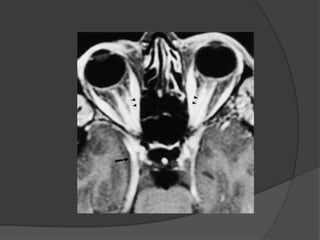

 CT findings:

 Segmental or diffuse

thickening of the optic

nerve.

 Fusiform but uniform

thickening of nerve

sheath more common.

 Normal optic nerve

running through the

tumor, have „ „tram-

track‟ „ appearance on

axial images.

 In coronal views a

“donut” configuration,

with a ring of high

density around nerve.

 Low-density normal

nerve surrounded by the

higher density tumor.

 This finding can

differentiating

meningioma from

glioma.

 MRI findings:

 Better for assessment of

intra-cranial extension.

enlargement.

 Fusiform thickening.

 On T1WIs, iso-signal with

gray matter.

 On T2WIs, iso to slight

bright signals.

 O post contrast, intense

enhancing criteria.

 „tram-track‟ on axial

imaging.

 “doughnut” configuration

on coronal scan.

 Intra-cranial extension

better detected on post

contrast scan.

Optic Nerve Sheath Meningioma: CT findings:  Segmental or diffuse thickening of the optic nerve.  Fusiform but uniform thickening of nerve sheath more common.  Normal optic nerve running through the tumor, have „ „tram- track‟ „ appearance on axial images.

Optic Nerve Sheath Meningioma: In coronal views a “donut” configuration, with a ring of high density around nerve.  Low-density normal nerve surrounded by the higher density tumor.  This finding can differentiating meningioma from glioma.

Optic Nerve Sheath Meningioma: MRI findings:  Better for assessment of intra-cranial extension.  Segmental or diffuse enlargement.  Fusiform thickening.  On T1WIs, iso-signal with gray matter.  On T2WIs, iso to slight bright signals.

Optic Nerve Sheath Meningioma: O post contrast, intense enhancing criteria.  „tram-track‟ on axial imaging.  “doughnut” configuration on coronal scan.  Intra-cranial extension better detected on post contrast scan.